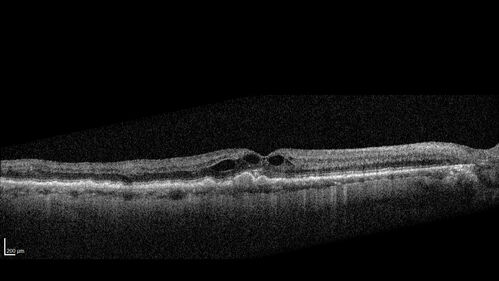

Hemi-CRVO - dual trunk vein

81 year old female mild vision loss - Anatomy shows dual trunk vein with one blocked. About 20 percent of people have this anatomy